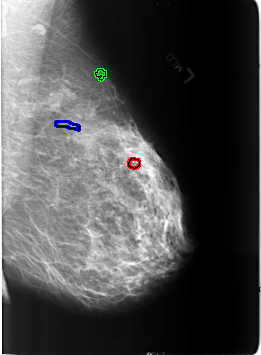

B_3240_1.LEFT_MLO

FILE: B_3240_1.LEFT_MLO.OVERLAY

TOTAL_ABNORMALITIES 3

ABNORMALITY 1

LESION_TYPE CALCIFICATION TYPE ROUND_AND_REGULAR-PUNCTATE DISTRIBUTION N/A

ASSESSMENT 2

SUBTLETY 4

PATHOLOGY BENIGN_WITHOUT_CALLBACK

ABNORMALITY 2

LESION_TYPE MASS SHAPE LYMPH_NODE MARGINS CIRCUMSCRIBED

ABNORMALITY 3

LESION_TYPE CALCIFICATION TYPE VASCULAR DISTRIBUTION N/A